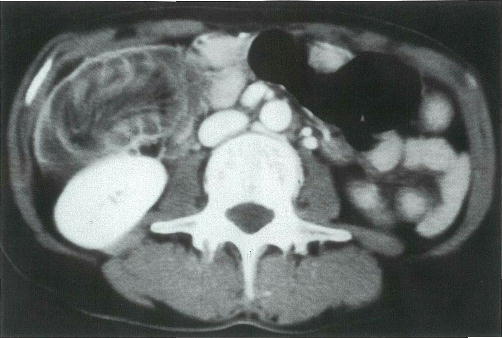

60歳の女性。昼食後に下腹部痛があり来院した。意識は清明。体温 36.7℃。脈拍 68/分,整。血圧 120/64mmHg。顔貌は苦悶様。腹部は平坦で,腸雑音はやや亢進している。右下腹部に圧痛があるが腹膜刺激症状はない。血液所見:赤血球 405万,Hb 13.8g/dl,Ht 35%,白血球 10000,血小板 17万。血清生化学所見:総蛋白 6.3g/dl,アルブミン 3.2g/dl,AST 32単位,ALT 27単位,LDH 430単位(基準 176~353),アルカリホスファターゼ 240単位(基準 260以下)。CRP 3.5mg/dl。腹部造影CTを別に示す。

最も考えられるのはどれか。

○ d

正解 d

診断 腸重積症